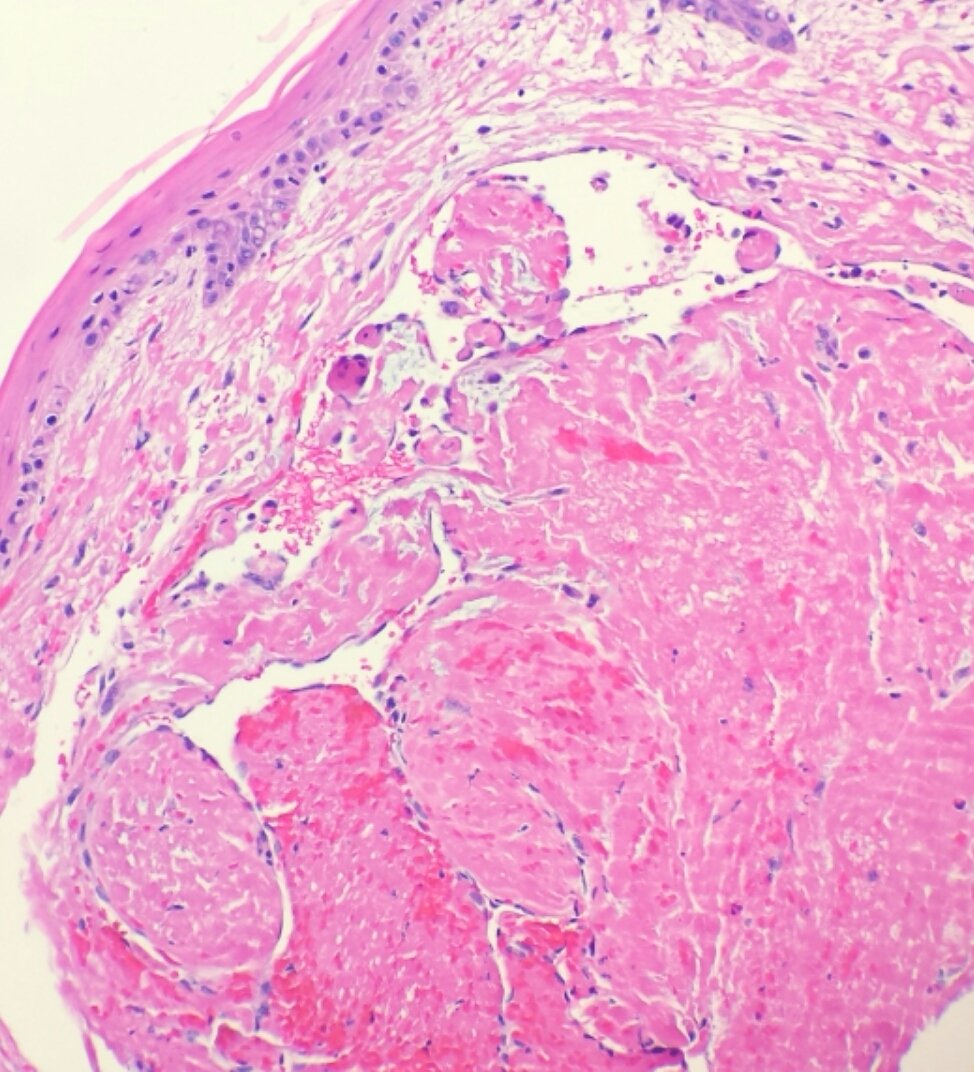

Карнификация Легкого: Микропрепараты и Диагностика

Раздел: Калейдоскоп образов